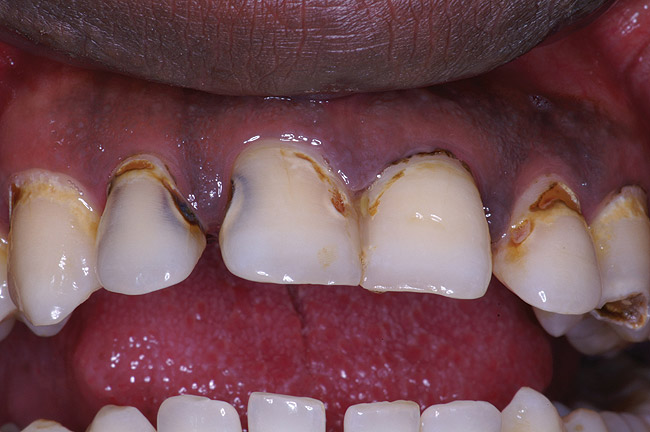

If a patient has risk factors that can contribute to dental erosion, an examination will reveal clinical signs and symptoms of dental erosion. It is unlikely that dental erosion will be seen without other contributing factors. Tooth wear and abrasion typically occur in combination with dental erosion. In the clinical evaluation of tooth surfaces for the diagnosis of erosion, what is typically seen are smooth, shiny surfaces of the teeth where the usual anatomic form of the tooth should be. In patients ingesting very acidic diets, the facial surfaces of anterior teeth are very smooth, and if the beverages being ingested have high sugar content, these teeth may have caries at their facial gingival margins (Figure 1). The occlusal surfaces of posterior teeth in the more advanced stages of erosion due to regurgitation may have extensive exposed dentinal areas with loss of anatomic form (Figure 2). In some cases, the chemical erosion combined with toothbrush–toothpaste abrasion can remove all the enamel, leaving only the dentin exposed (Figure 3). These teeth may exhibit sensitivity. Posterior teeth with restorations may demonstrate fillings that are higher than the surrounding occlusal surfaces of the enamel. Anterior teeth may demonstrate more incisal translucency due to tooth loss at the incisal edge. In patients with the eating disorder bulimia nervosa, who vomit, the hydrochloric acid causes extensive damage to the lingual surfaces of the anterior teeth, where the enamel is lost, leaving exposed dentin (Figure 4).

Figure 2  This patient with a history of chronic alcoholism and frequent night vomiting has dissolved the occlsual surfaces of his posterior teeth.

Figure 2